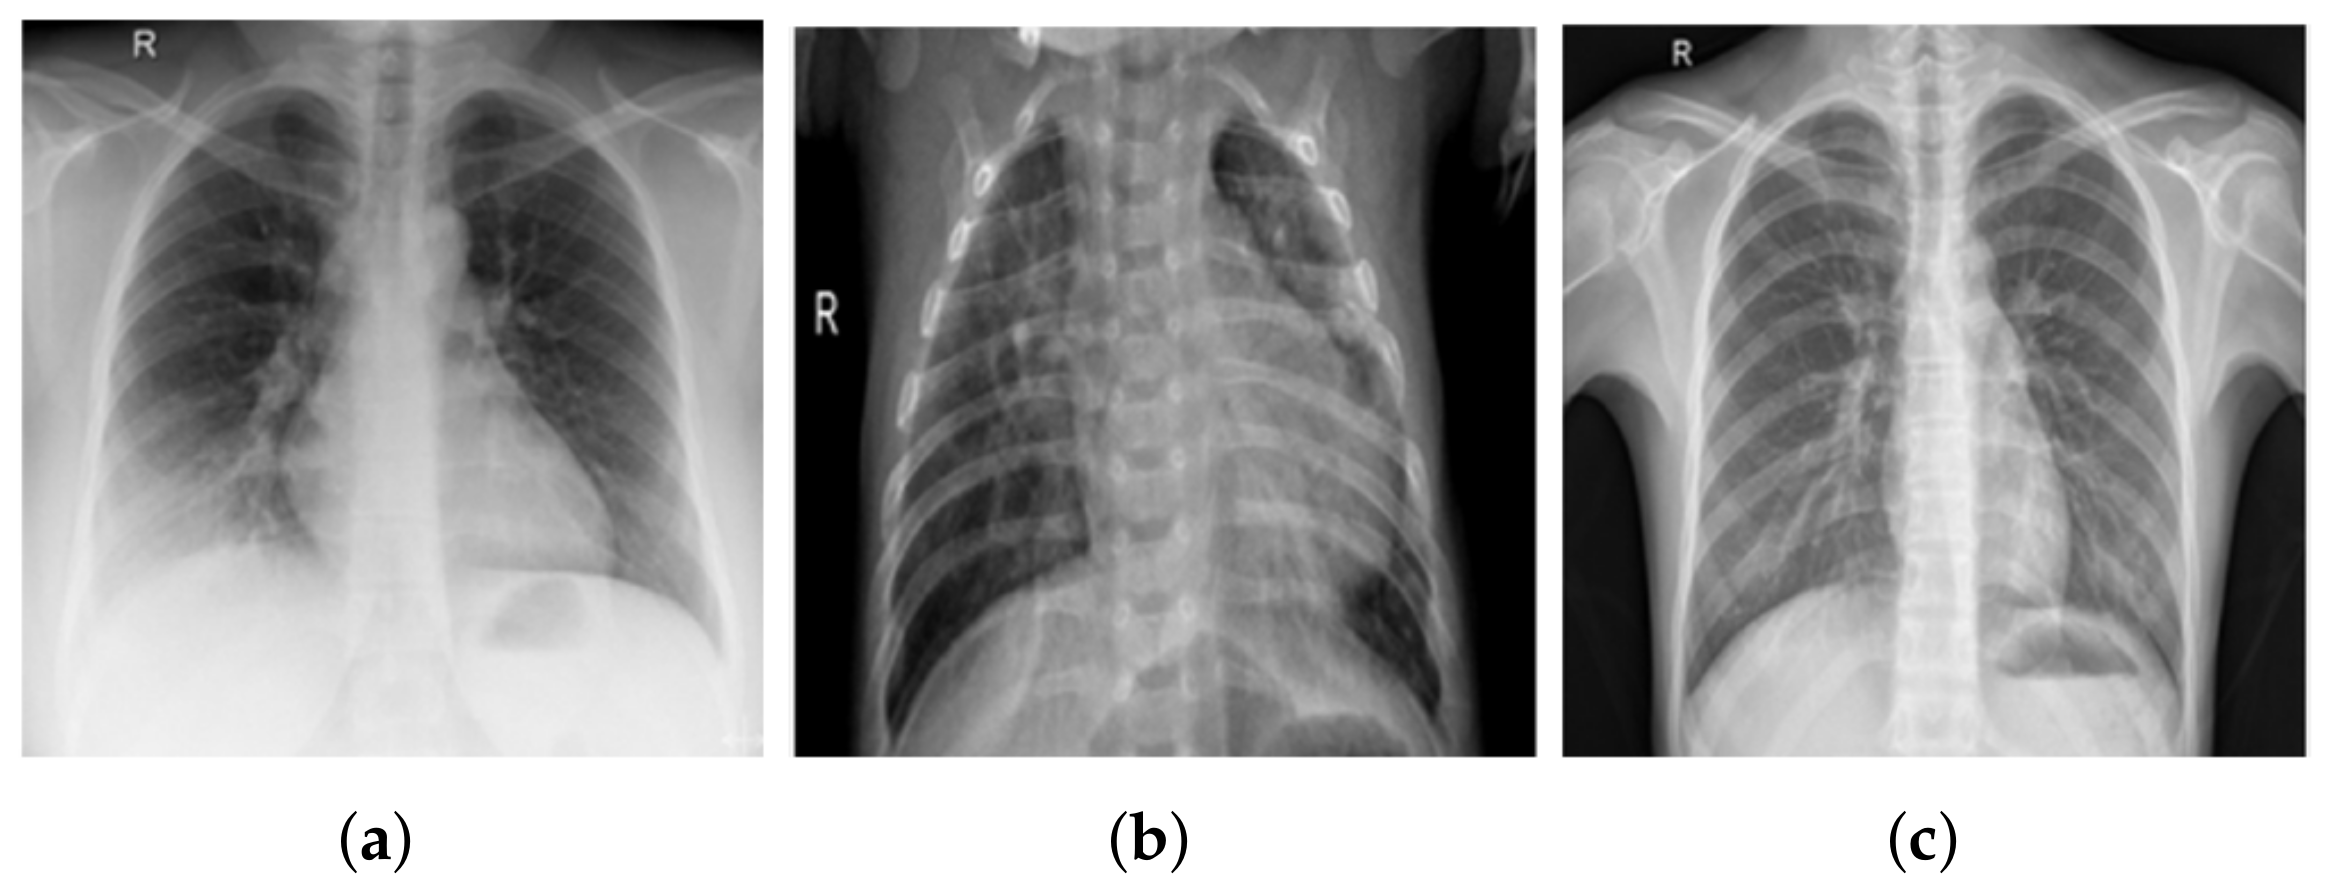

3.1. COV-PEN Image Datasets

3.2. Image Preprocessing Step